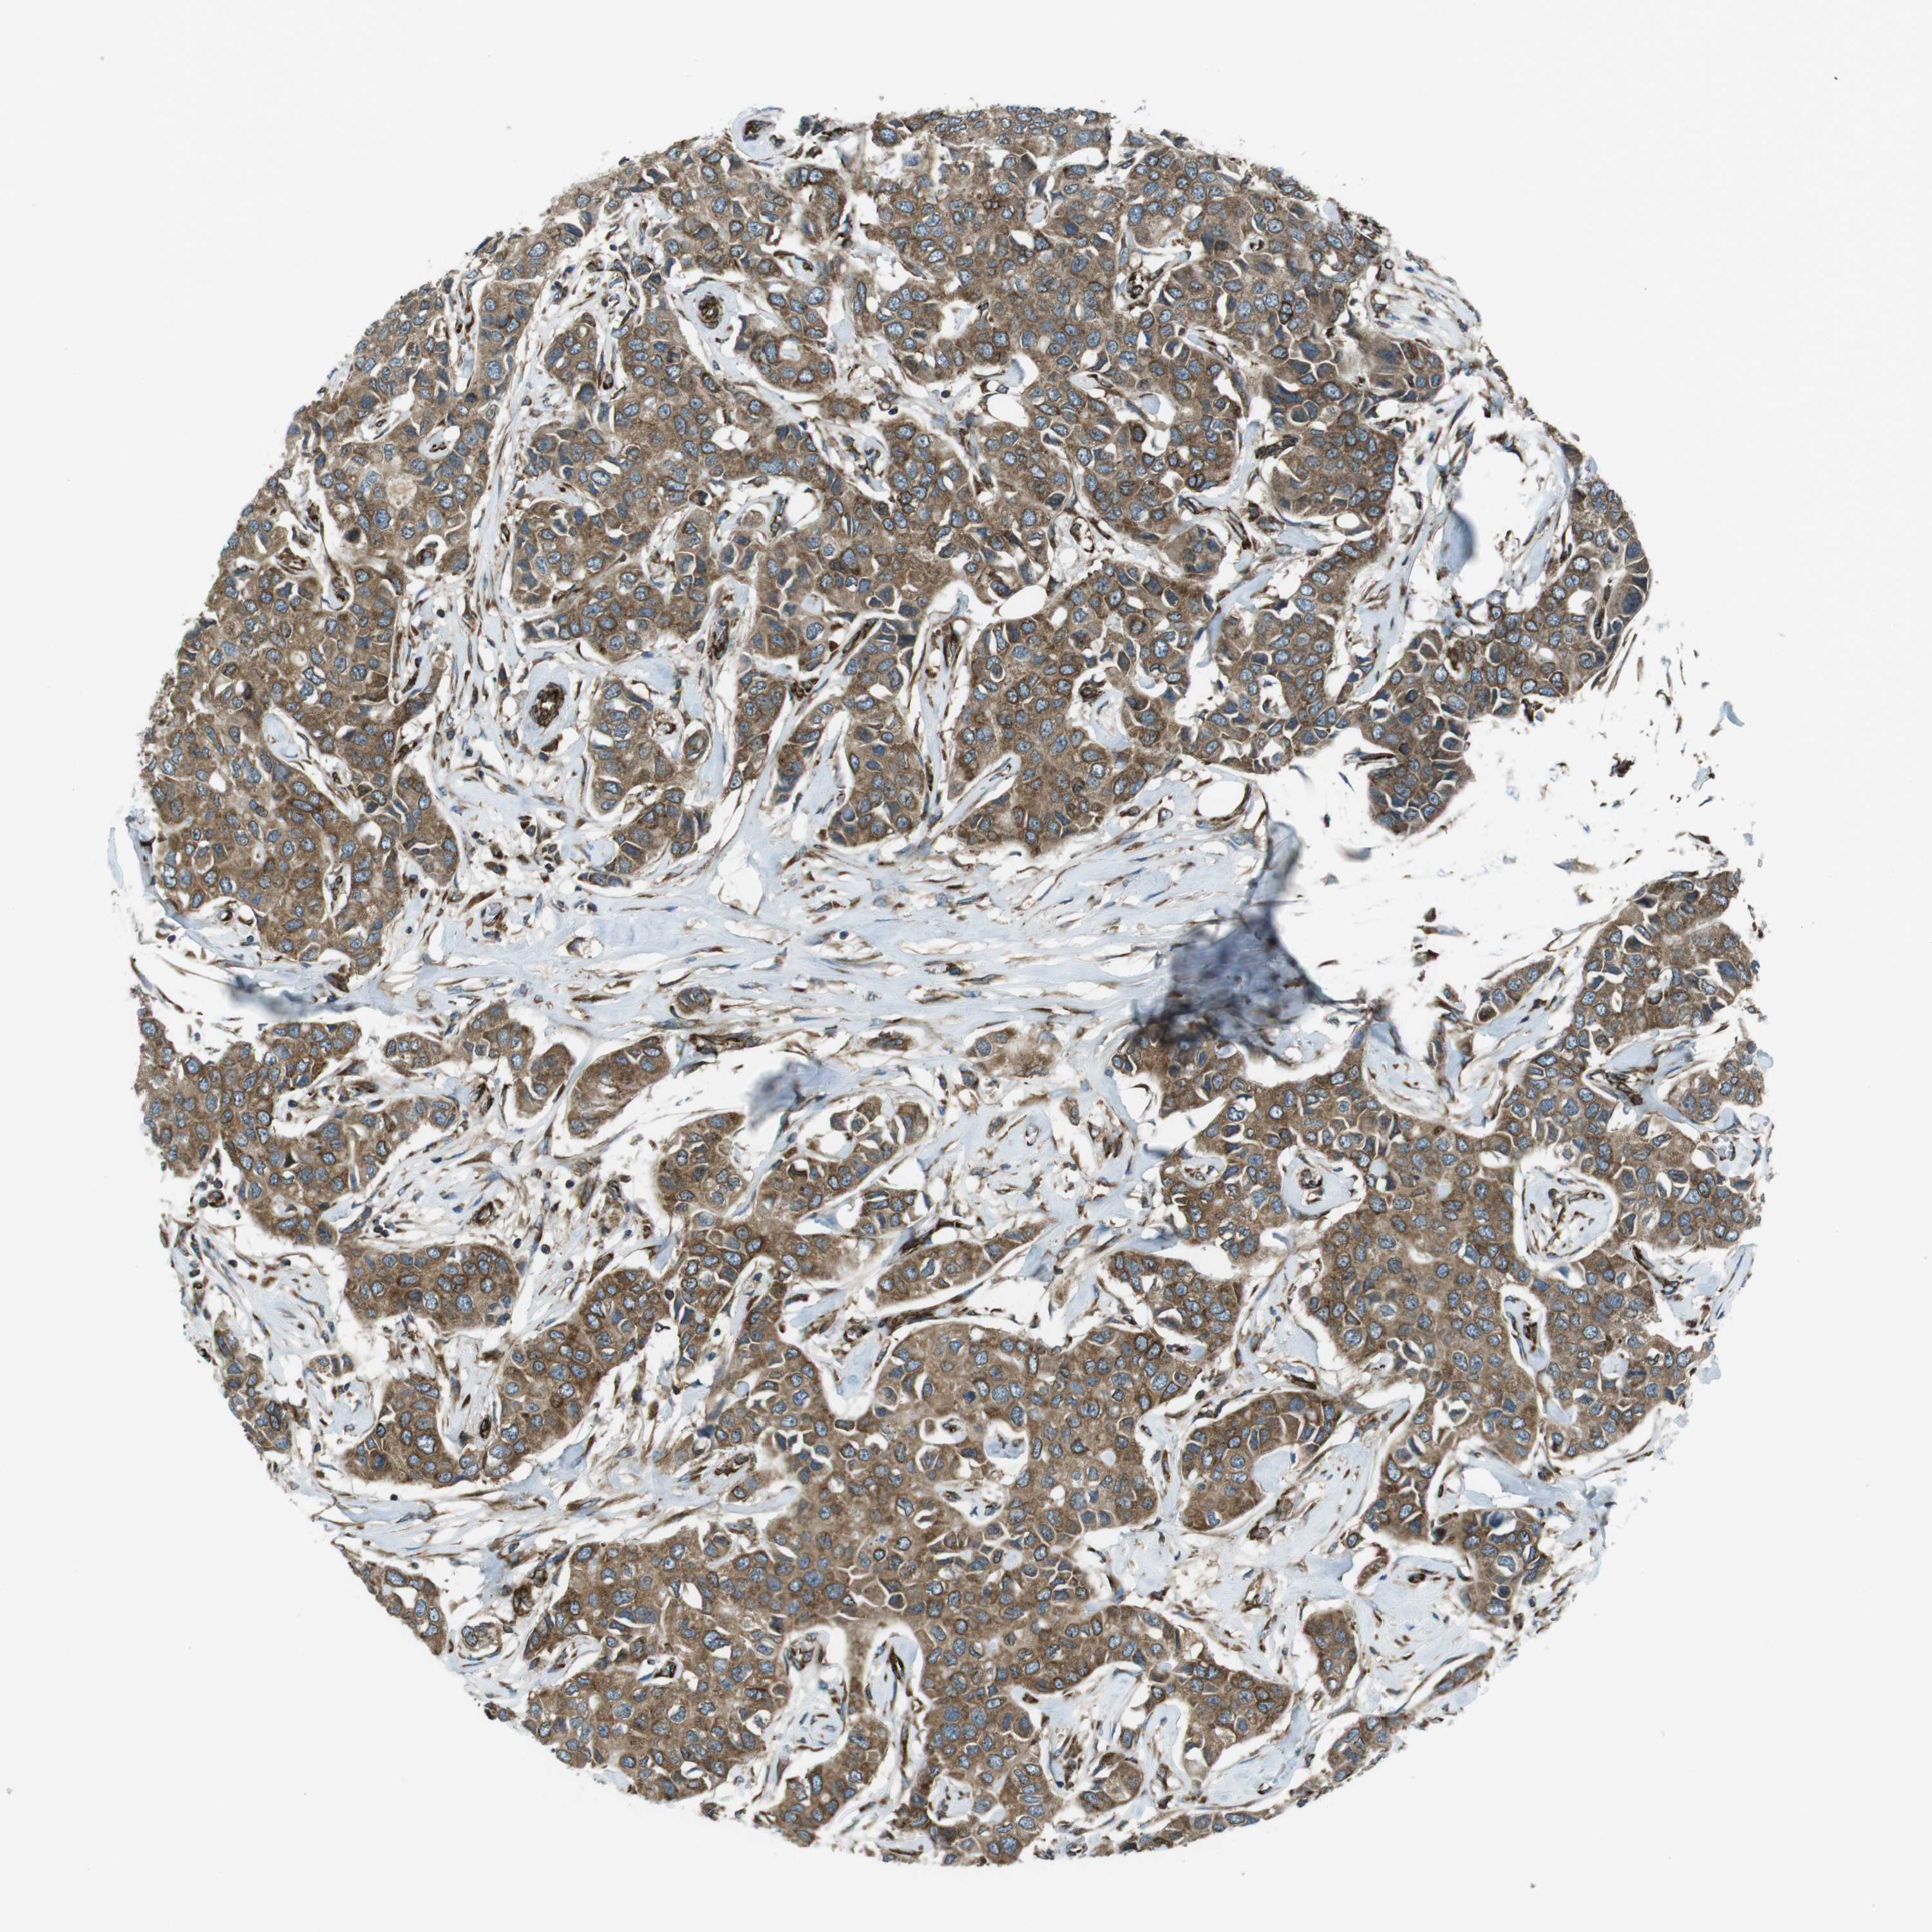

CANCER BREAST CANCER Show tissue menu

BRCA TCGA BRCA VALIDATION PROTEIN EXPRESSION